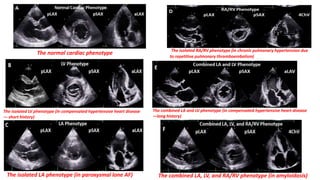

Echo phenotypes “Clinical Research in Cardiology , Published: 04 June 2022”

The normal cardiac phenotype

The isolated LV phenotype (in compensated hypertensive heart disease

— short history)

The isolated LA phenotype (in paroxysmal lone AF)

The isolated RA/RV phenotype (in chronic pulmonary hypertension due

to repetitive pulmonary thromboembolism)

The combined LA and LV phenotype (in compensated hypertensive heart disease

—long history)

The combined LA, LV, and RA/RV phenotype (in amyloidosis)